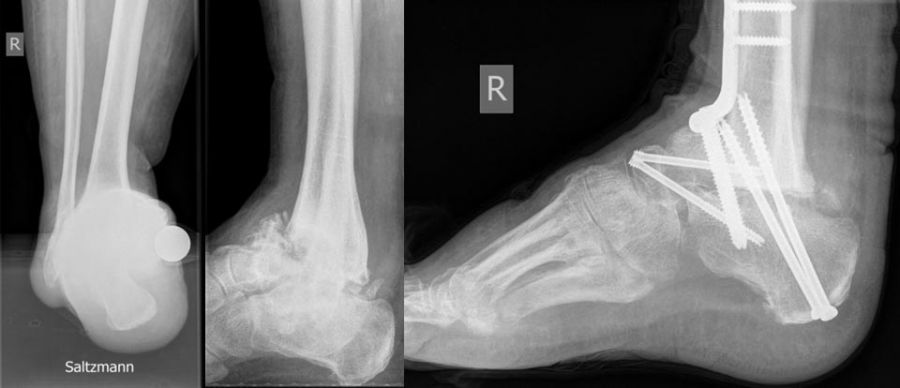

- Operative Behandlung von Druckstellen durch den Zusammenbruch des Fußlängsgewölbes

Als Folge der diabetesbedingten Neuropathie kann es zu dem sogenannten Charcotfuß kommen. Bei dieser Komplikation der Diabeteserkrankung kommt es häufig zu einer Zerstörung der Fußwurzelgelenke und -knochen. Dabei springen die Knochen aus den Gelenken (Luxation) und brechen (Fraktur). Der Fuß verliert an Halt und das Fußgewölbe kann zur Fußsohle durchbrechen (Plattfuß). Hierbei treten Druckstellen durch überstehende Knochenfragmente an der Fußsohle auf, die dann zu Hautschäden führen. Sollten hier konservative Therapiemaßnahmen (Polsterung/Schuhzurichtung) versagen, ist eine operative Korrektur angezeigt. Dabei werden die Knochen mittels Platten und langen Schrauben stabilisiert.

Zum Lesen der Bildbeschreibung und Vollansicht bitte Bild anklicken. Fotos: Alexander Mehlhorn

- Operative Behandlung von Druckstellen durch Fehlstellungen/Instabilität des Rückfußes bzw. Sprunggelenk

Eine weiterer typischer Verlauf eines Charcot Fußes betrifft die Zerstörung der Bänder und des oberen Sprunggelenks. Der Fuß knickt dabei nach innen, manchmal auch nach außen weg. In Schuhen kommt es meist zu Druckstellen im Bereich des Knöchels. Teilweise ist das Sprunggelenk ist so instabil, dass Laufen nicht mehr möglich ist. Oft sind hier die Möglichkeiten einer konservativen Therapie mit Polsterung/Schuhversorgung nicht mehr ausreichend. Kann der Fuß von außen nicht mehr ausreichend stabilisiert werden, ist eine operative Stabilisierung der abgekippten Gelenke mit Platten und Schrauben notwendig um wieder einen belastbaren Fuß zu erreichen.